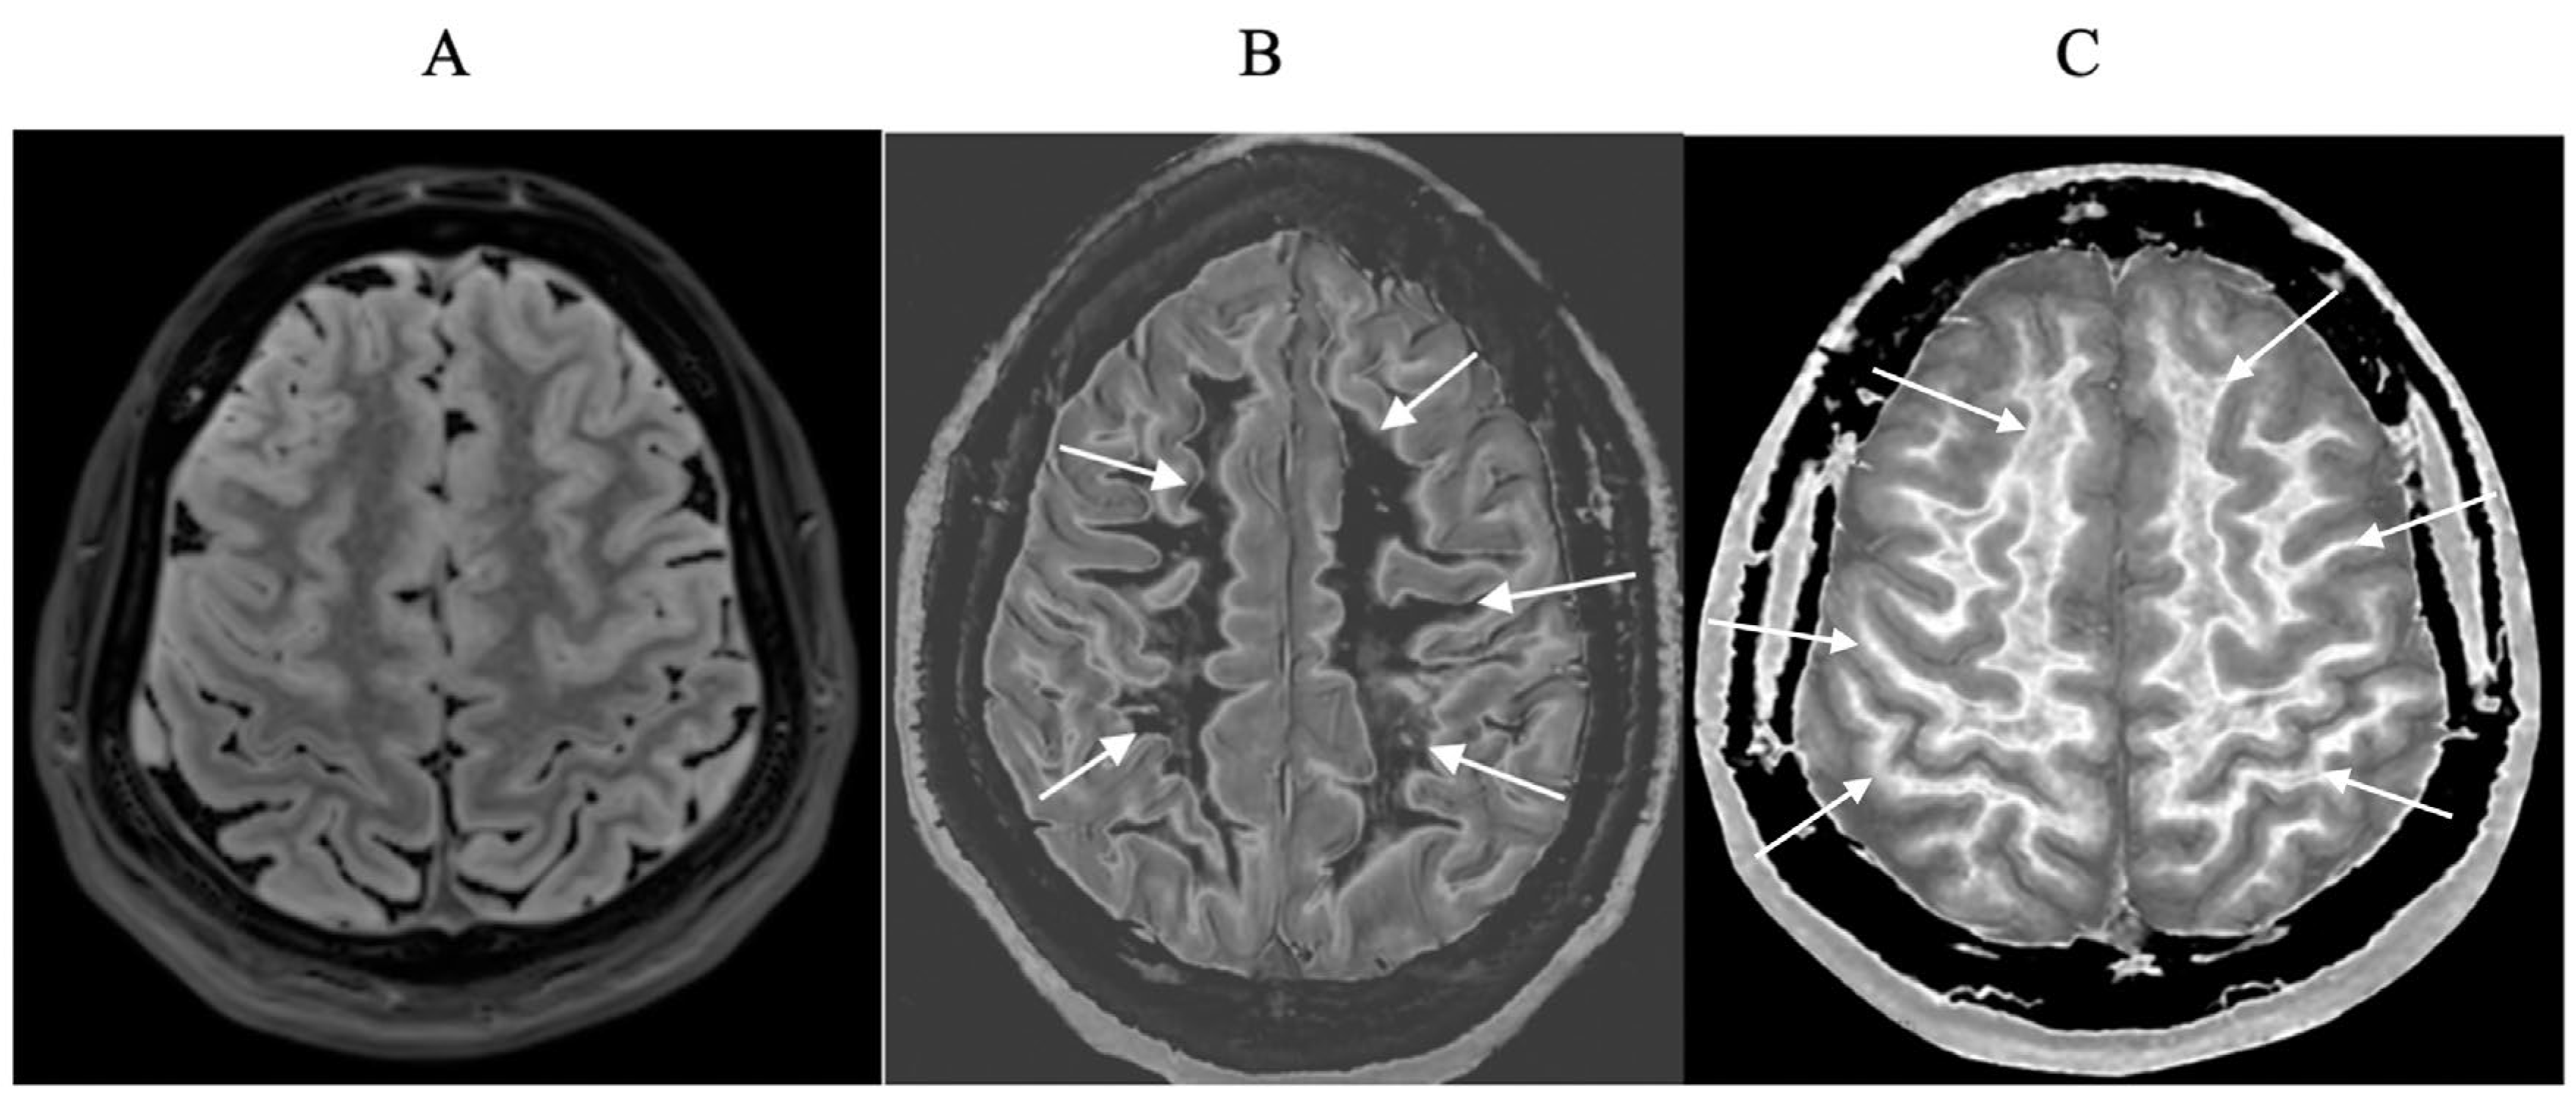

Figure 16.

32-year-old female with MS during a relapse. T

2-FLAIR (A), synthetic narrow mD dSIR (B) and filtered gradient echo (C) images. On the T

2-FLAIR image (A), one lesion is seen (long arrow). The surrounding white matter appears normal. On the dSIR image (B), the lesion shown on the T

2-FLAIR image is seen (long arrow) as well as six other lesions (short arrows). High signal boundaries around lesions are also seen in (B). Some of these lesions show paramagnetic rims on the filtered gradient echo image (arrows) in (C). In addition, most of the white matter in (B) is high signal corresponding to a high grade 4/5 whiteout sign [

1]. The whiteout sign is not seen on the T

2-FLAIR image (A).